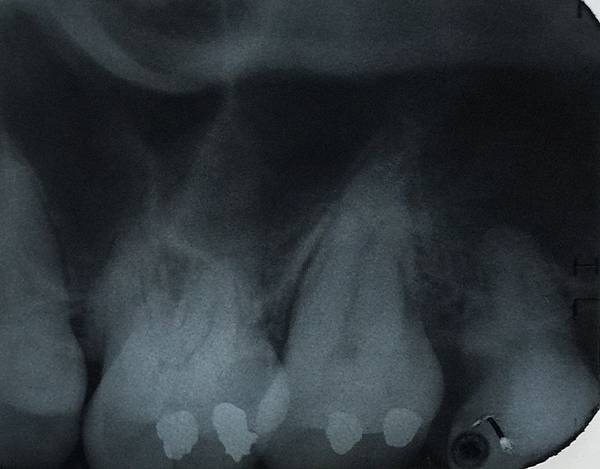

拔牙後的傷口是一個深洞

膠原蛋白敷料就是在拔牙後

塞到傷口裡填滿這個空間

未來癒合的過程中

骨頭跟牙肉生長的分量也會增加